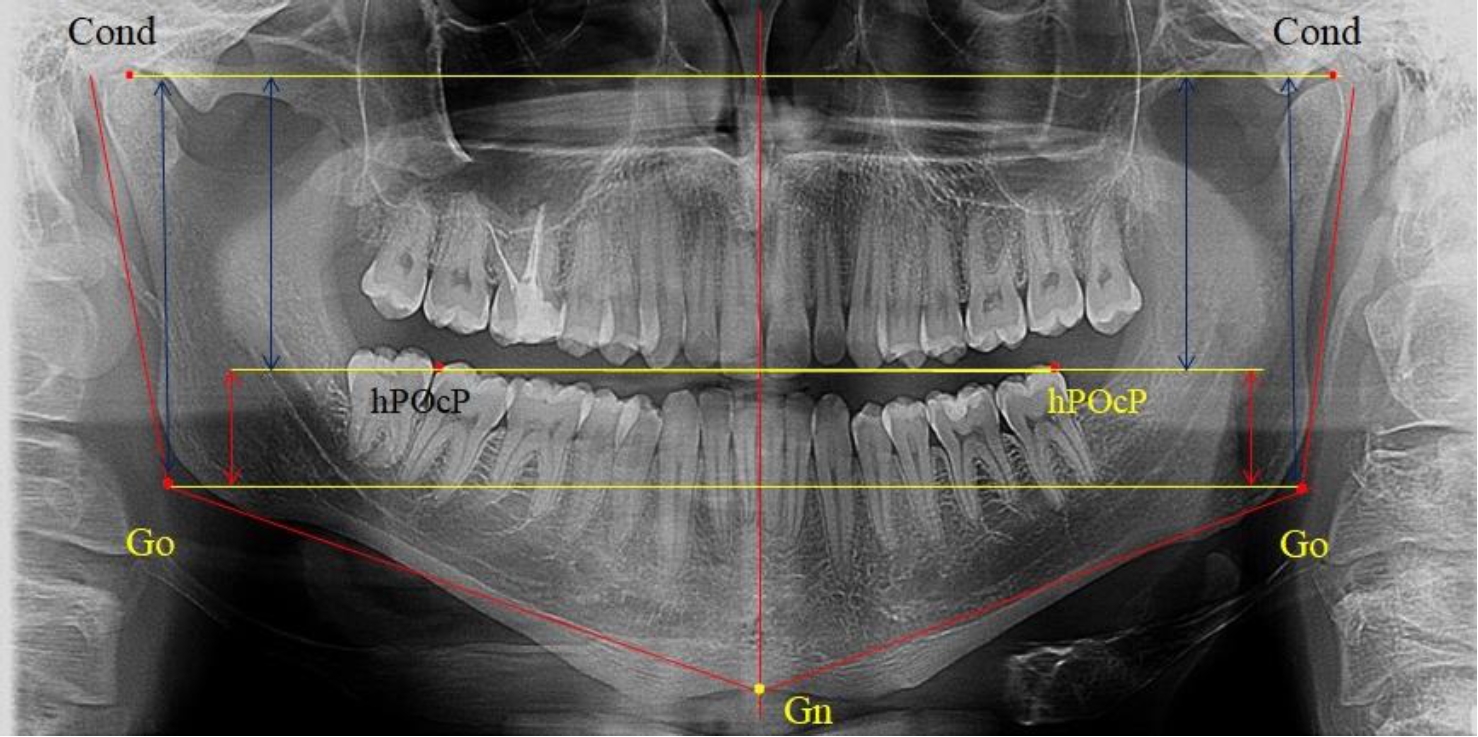

На ортопантомограмме использовали аналогичные суставные точки Cond на каждой стороне, их соединяли между собой суставной линией Cond-Cond.

Касательная к ветви нижней челюсти соединяла выступающие точку. При построении касательной к телу челюсти проводили в обе стороны линии от точки Gn, расположенной в нижней центральной части подбородочного симфиза, до выступающей нижней точки угла челюсти. Касательные линии при пересечении определяли конструктивную точку гонион Go. Соединение гониональных точек определяло положение гониональной линии Go-Go. При соединении окклюзионных точек hPOcP получали окклюзионную горизонталь (рис. 1). Измеряли расстояние между горизонталями в области ветвей нижней челюсти. Статистический анализ проводили в программе Microsoft Excel. Составляли вариационные ряды с последующим расчетом среднего значения, стандартного отклонения и ошибки среднего ±m. Также оценивали максимальные и минимальные значения величин. Определи относительные величины соотношения верхней и нижней частей ветви нижней челюсти.

Рис. 1. Метод измерения высоты ветви нижней челюсти на телерентгенограмме (а) и ортопантомограмме (б)

В 1-ю подгруппу были включены 36 комплектов телерентгенограмм и ортопантомограмм [или (48,65 ± 5,81) % от общего количества], на которых средняя величина отношения верхней части ветви к нижней составляла 1,95 ± 0,03, что соответствовало показателям, полученным по группе в среднем, но с меньшим показателем ошибки среднего значения. Визуально верхняя окклюзионно-суставная часть выглядела вдвое больше нижней окклюзионно-гониональной (рис. 2). При этом высота ветви составляла (62,09 ± 1,22) мм. Максимальная высота была 71 мм, а минимальная – 55 мм. Высота верхней части составляла (41,02 ± 0,77) мм, а высота нижнего отдела ветви была (21,09 ± 0,51) мм.

Рис. 2. ОПТГ пациента 1-й группы с оптимальным коэффициентом соотношения частей ветви нижней челюсти